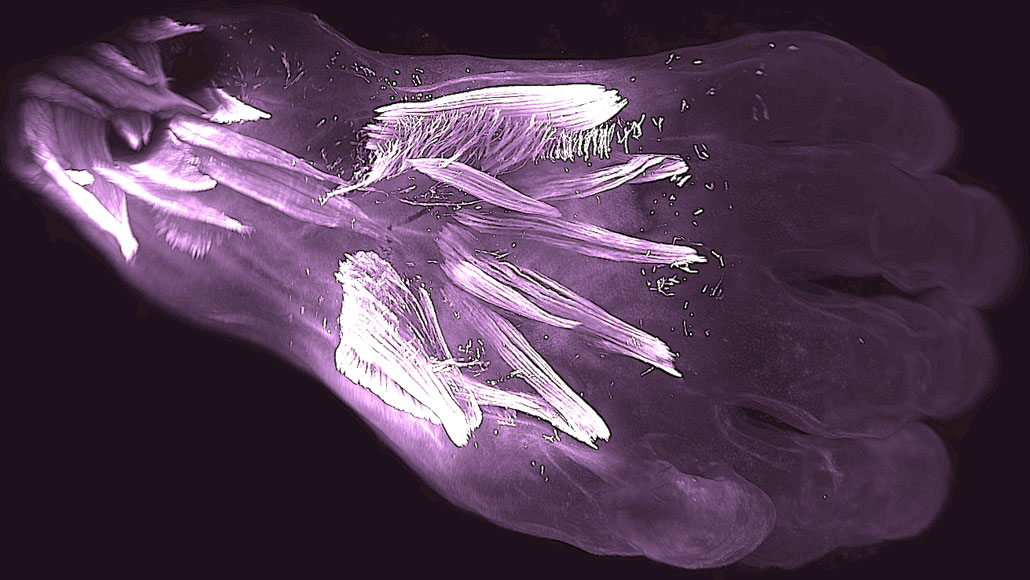

Muscles in the back of a 10-week-old human embryo’s hand called dorsometacarpales (the two smallest horizontal muscles highlighted at center) will be lost or fuse with other muscles during development.

Other animals have kept some of those muscles. Adult chimpanzees and human embryos have epitrochleoanconeus muscles in their forearms, but most adult humans don’t. Human’s mammalian ancestors also lost dorsometacarpales muscles from the back of the hand about 250 million years ago as mammals and reptiles split on the evolutionary tree. Lizards still have those muscles, and they appear in human embryos, but then are lost or fuse with other muscles during development and aren’t found in most adults.